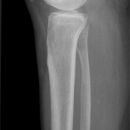

Unterschenkel lateral (medio-lateral, 2. Ebene)

Deckungsgleiche Darstellung der Femurkondylen. Distaler Unterschenkel mit seitlicher Projektion des Sprunggelenkes. Die Fibula projiziert sich in Höhe des Sprunggelenks auf das mittlere bis hintere Drittel der Tibia.